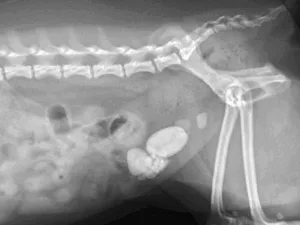

皮膚肥満細胞腫

肛門付近の皮膚腫瘤

脱毛を伴う、明らかな腫脹は認められず

細胞診検査で肥満細胞腫と診断